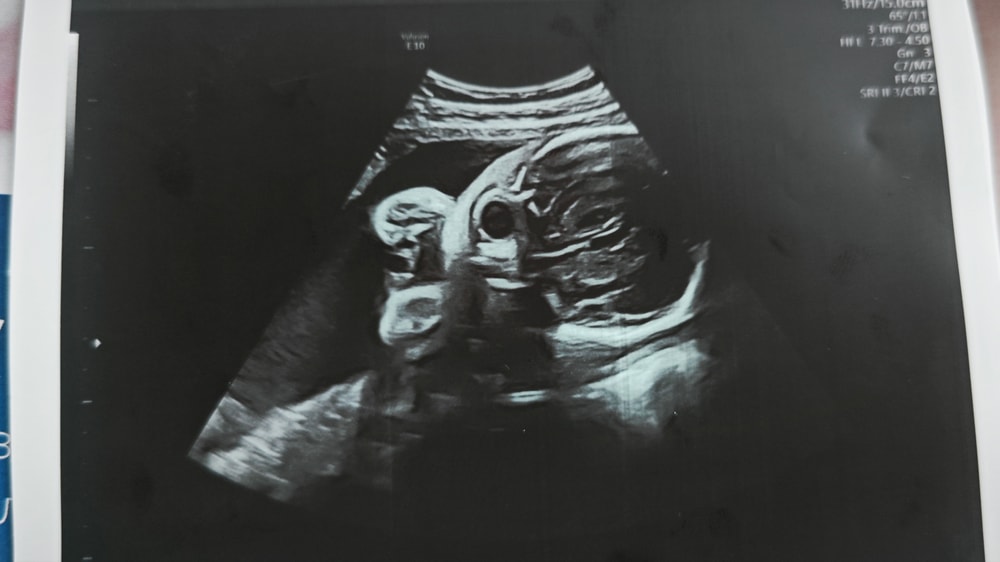

Сходила в частную клинику на УЗИ в 28 недель, сказали, что всё хорошо ттт, и дали фото. И вот когда я уже вышла с клиники и увидела фото, я вообще ничего не поняла. Это вроде голова, но вообще непонятно что где и выглядит жутковато...

Может тут кто-то разбирается или понимает что где на этих фото?

Просто не самый удачный ракурс распечатали вам, не бойтесь)

Я понимаю, что это череп. Но, с какого ракурса понять не могу🤣

Голова и ручки около лица. Голова у них на узи со всем содержимым видна🤣, потому и жутковато выглядит🤣🤣🤣